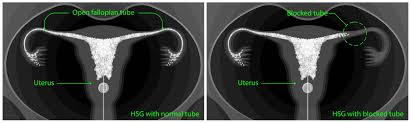

Infertility occurs primarily from the combination of fibroids, ovarian cysts, tubal blockage, and sometimes a hot stomach.

They’ll also face the womb conditions to get through, and all this would only be possible if the fallopian tubes are open.